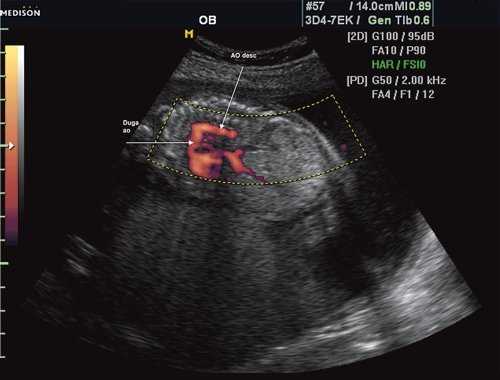

Рис. 1. Восходящий отдел, дуга и нисходящий отдел аорты плода в режиме энергетического допплера в норме.

Согласно "теории дуктальной ткани" коарктация аорты возникает в результате миграции гладких мышечных клеток протока в предуктальную аорту, с последующей констрикцией и сужением просвета аорты [4]. При формировании коарктации аорты в области перешейка сохраняется сужение различной протяженности и формы (рис. 2, 3). Наиболее часто это проявляется в виде локальной перетяжки, выше или ниже которой диаметр аорты сохраняется в норме.

Рис. 2. Ультразвуковое исследование восходящего отдела, дуги и нисходящего отдела аорты. Стрелкой указано место сужения.

Рис. 3. Трехмерное изображение сердца и аорты плода в 16 нед беременности. Стрелкой указано место сужения аорты. AO DESC - нисходящий отдел аорты, COR - сердце.